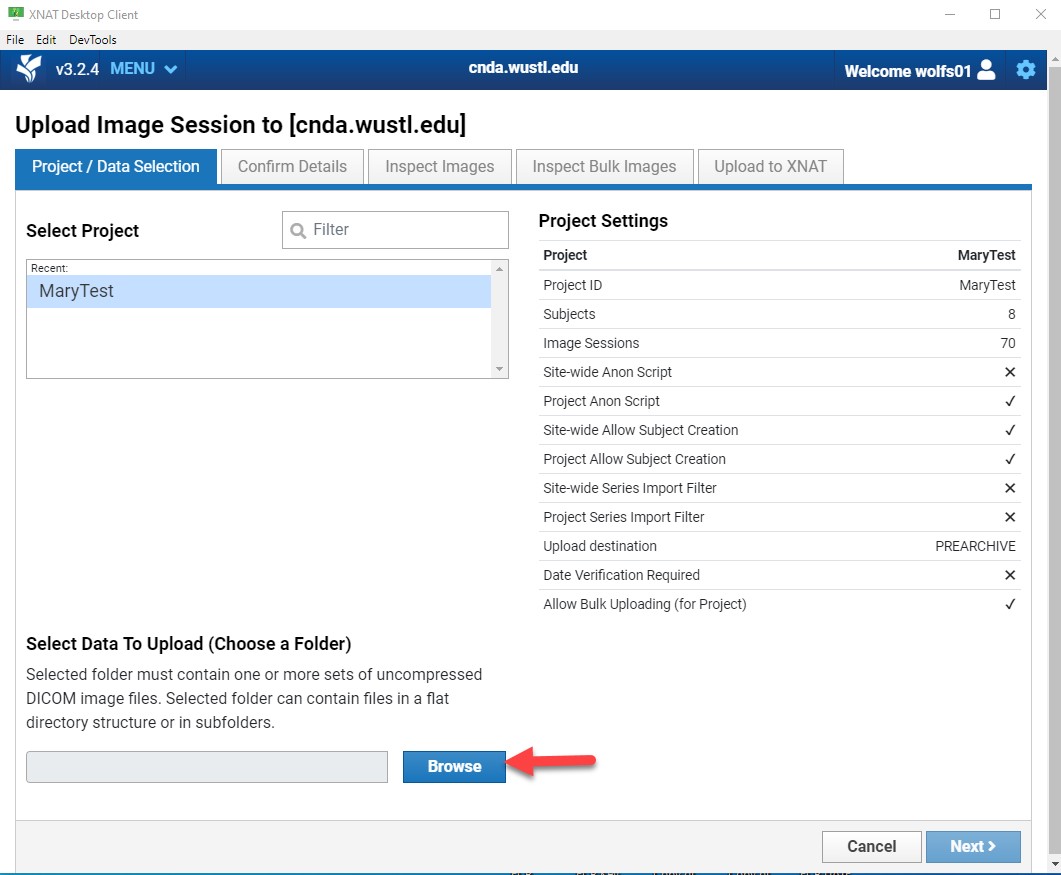

Start Upload

- Click Upload Files.

- Select the destination Project.

Only projects you have access to will appear.

- Click Browse and select the directory containing your image files.

- If prompted with anonymization options, select the file and click Upload.